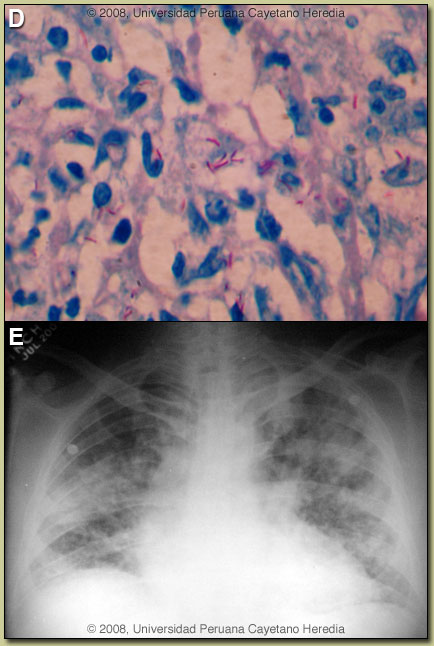

Discussion: Image B demonstrates a single ulcer located in the non-mesenteric border of the ileum with necrotic borders partially covered by fibrin. Microscopy [Image C] demonstrates a perforated intestinal ulcer surrounded by acute and chronic inflammation and epithelioid cells, with no well-formed granulomas. Examination of lymph nodes showed a necrotizing suppurative adenitis also without granuloma formation. Ziehl Nielsen stain of the intestine and lymph node were highly positive [Image D]. Sputum is Z-N positive.

On further enquiry one of his sons is currently being treated for smear positive pulmonary TB. The patients chest X-ray is shown [Image E] demonstrating a miliary pattern with bilateral alveolar infiltrates. HIV ELISA is positive; the patient had not previously been tested. In Perú, the main differential diagnosis in a patient with this initial clinical presentation (without knowledge of the chest X-ray findings) would be typhoid fever due to Salmonella typhi complicated by intestinal perforation. Involved Peyer’s patches are generally in the terminal ileum within 60 cm of the ileo-cecal junction and in the cecum itself. Without treatment, after about 7-10 days of illness, necrosis and sloughing of the overlying mucosa may result with ulcer formation and more rarely intestinal perforation. Ulcers are usually 1 cm or less in size and most often solitary. Intestinal perforation due to E. histolytica would usually be preceded by a hemorrhagic colitis and perforation due to Balantidium coli by profuse watery diarrhea [see Gorgas Case 2002-07]. Prevalence data for intestinal TB are sparse either in HIV positive or negative patients but in 1 referral center in Hong Kong it was ~0.5% of presenting cases [see Hong Kong Med J. 2006 Aug;12(4):264-71]. Perforation is rarely seen in our experience but a recent surgical case series from South Africa in HIV positive patients included 4 with perforation [see World J Surg. 2007 May;31(5):1087-96]. Intestinal TB is usually an intraluminal disease that presents with fever, diarrhea, and sometimes intestinal obstruction. Intestinal TB is distinct from peritoneal TB [see Gorgas Case 2004-04], which is thought to most often occur by seeding after rupture of and intra-abdominal lymph node. There are three ways for bacilli to reach the intestine (ingestion, hematogenous and spread from a contiguous focus); the hematogenous route is most likely in this case. There are three macroscopic forms of intestinal TB; ulcerative (most common), hypertrophic and mixed. Involvement of the ileocecal region is most common (90% of all intestinal cases), usually accompanied involvement in draining lymph nodes. This patient has disseminated TB (pulmonary, lymph node, intestinal) and the HIV and the lack of granulomas indicate a low CD4-count (not available yet). Treatment includes antibiotics as would be used for any interstinal perforation plus standard TB therapy. HAART is deferred until completion of the first 2 months of TB therapy in order to avoid a severe immune reconstitution syndrome in a patient with such a high bacillary load. HIV increases risk of progression of those infected with TB to active tuberculosis (10% per year in HIV positive vs. 10% life-time in HIV negative individuals). In Perú, approximately 40% of HIV patients develop active TB at some time. Conversely, TB infection induces increased HIV replication. HIV is the leading cause of hospitalization on our Infectious Diseases unit; TB is the leading opportunistic infection in these patients. The clinical presentation of TB varies according to CD4 count. Typical pulmonary disease with cavities is seen in patients with CD4>200, disseminated (more than one focus or hematogenous spread) with bilateral pulmonary infiltrates and mediastinal-pleural involvement is seen in those with lower CD4 counts and especially with < 100 CD4 cells. A positive PPD in HIV-infected patients with miliary TB is seen in less than 10%, positive sputum smears are seen only in 25%, blood cultures tend to be positive in 50-60%. Post-operatively this patient was treated with broad spectrum antibiotics and 4-drug TB therapy. The course was complicated by dehiscence of the anastomoses requiring an ileostomy. Fistula to adjacent organs, dehiscence of sutures, sepsis, malnutrition and high mortality are reported in these patients. |